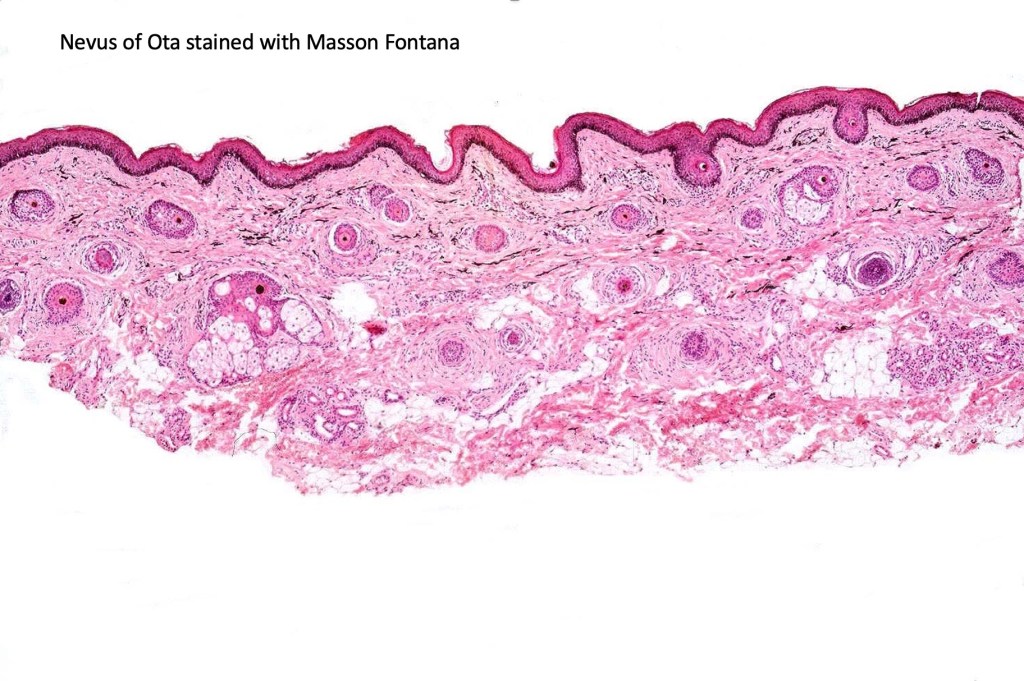

Histologically the features are very subtle and may require a Masson Fontanna stain or immunohistochemistry for diagnosis. Small numbers of dendritic melanocytes are present in the deep dermis siad to be orientated parallel to the epidermis.

Histologically, both lesions are characterized by the presence of denritic melanocytes in the upper & mid dermis. The overlying epidermis is often hperpigmented and increased numbers of melanocytes are sometimes evident.